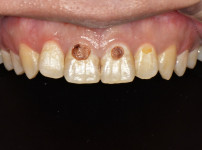

상악전치부 심미보철

최OO님/치료기간:2주/상악전치...